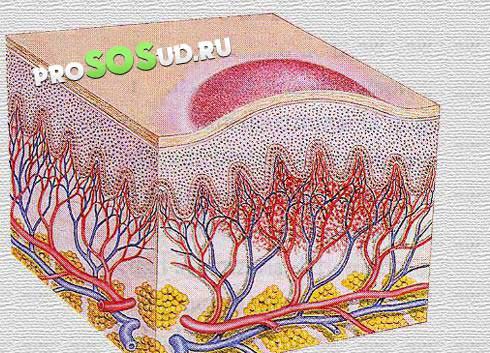

Врачи выделяют три основных типа ангиом: капиллярные, кавернозные и венозные. Каждый из этих видов имеет свои особенности и потенциальные риски. Капиллярная ангиома затрагивает сеть мелких капилляров, тогда как кавернозная форма представляет собой пещеристое образование багрового цвета с нарушенным кровотоком внутри.

Венозный тип характеризуется тёмно-синим или коричневым оттенком и способен к самостоятельному прогрессированию, что может привести к инсульту.